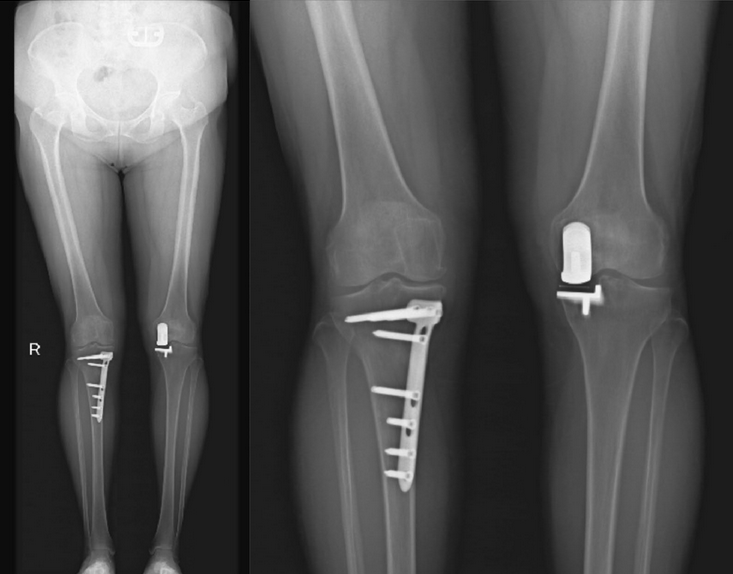

图1 HTO和UKA术后图像。A为下肢全身x线片,B为膝关节负重正位x线片